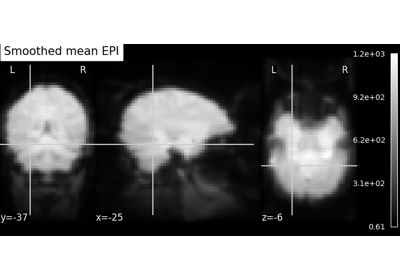

Exercise: Varying the amount of smoothing in an image

Compute the mean EPI for one individual of the brain development dataset downloaded with nilearn.datasets.fetch_development_fmri and smooth it with an FWHM varying from 0mm to 20mm in increments of 5mm

Intermediate steps:

1. Run nilearn.datasets.fetch_development_fmri and inspect the .keys() of the returned object

2. Check the nilearn.image module in the documentation to find a function to compute the mean of a 4D image

3. Check the nilearn.image module again to find a function which smoothes images

4. Plot the computed image for each smoothing value

A solution can be found here.